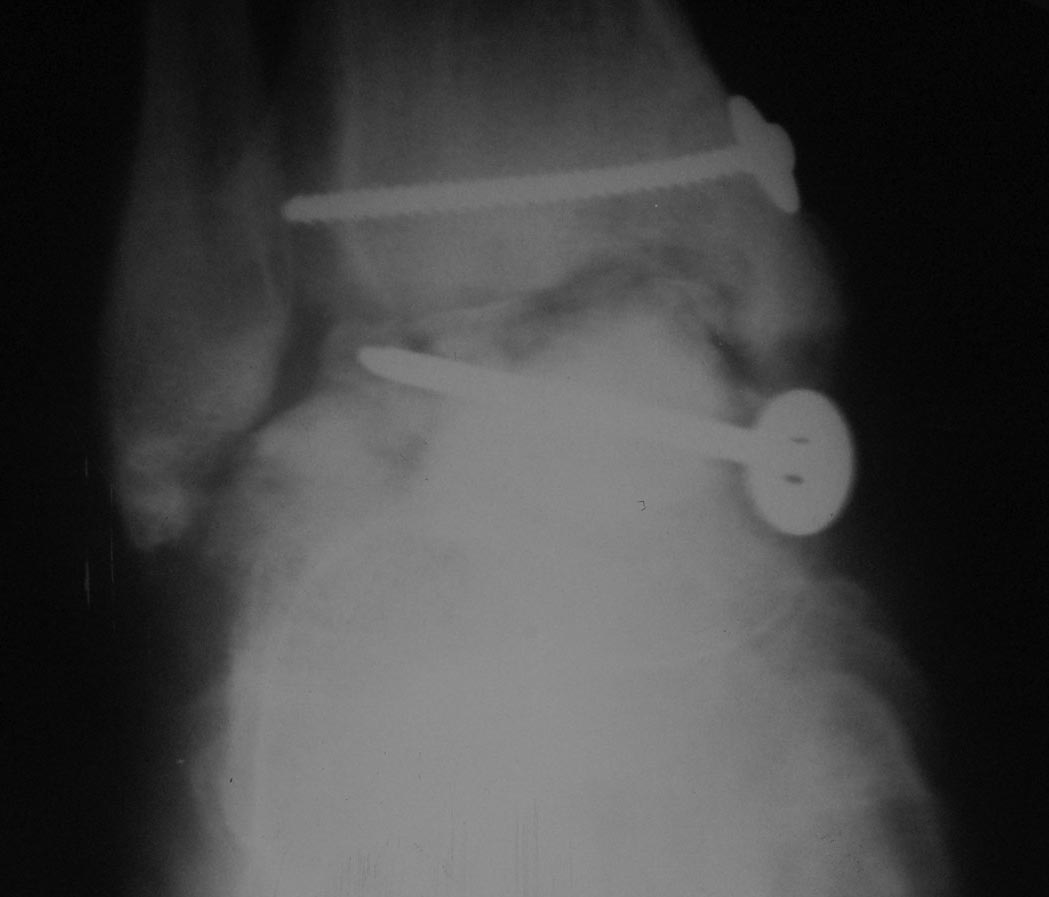

[Ortho] Последствия переломовывиха таранной кости

Извините "корявые" руки травматолога и нет не дружат:). Выкладываю

первичный снимок. Если можно более конкретно методики артродезов. Делали

все кроме стержня. И основной вопрос как определить границу

жизнеспособной таранной кости???